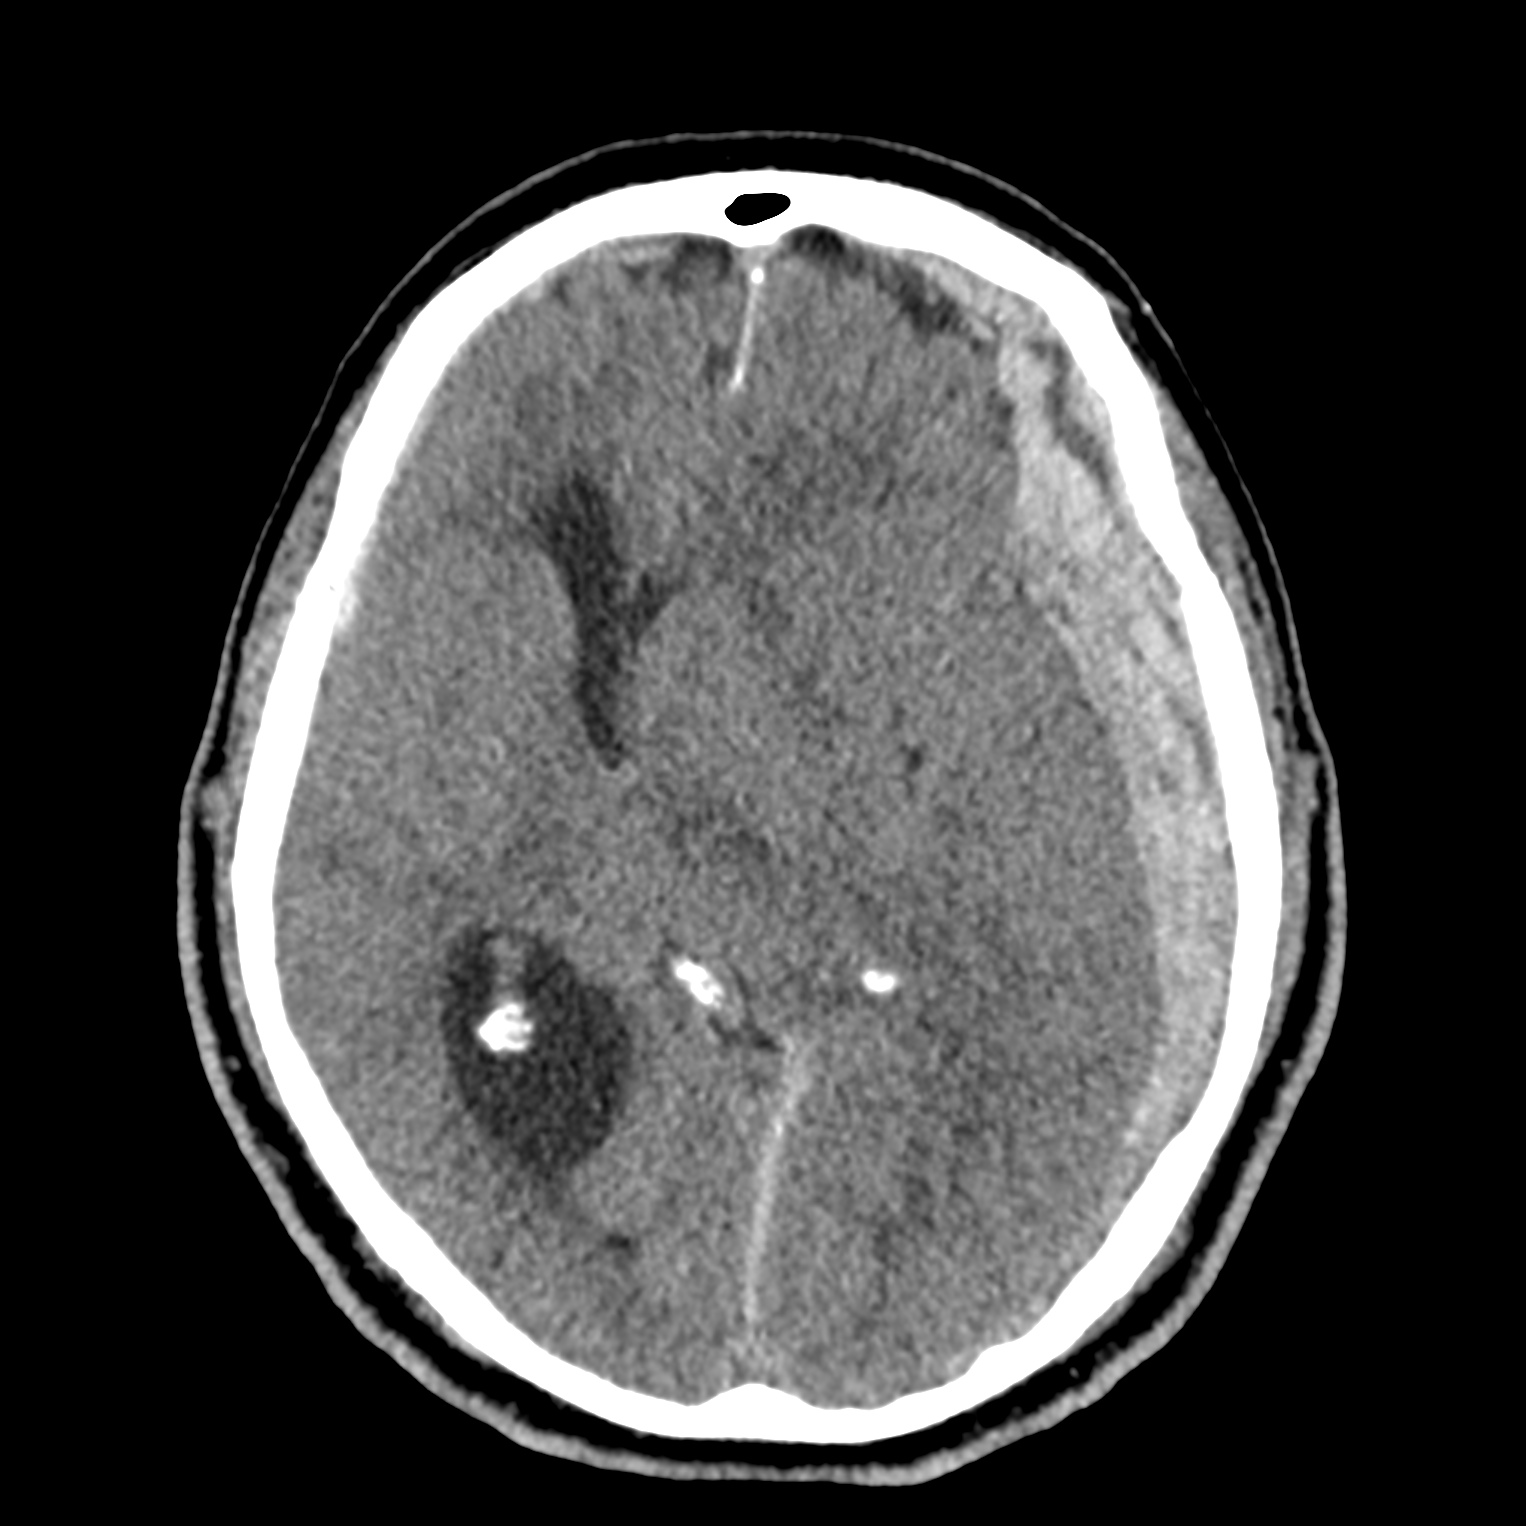

ちなみに画像診断とは、CTやMRIなどの画像を見て、正常か異常か、異常であればそれが何なのかを診断する仕事です。

Case courtesy of Andrew Dixon, Radiopaedia.org. From the case rID: 32383

医療従事者でなければ何のメリットも無いかもしれないのですが、実際の画像を自分でスクロールしながら学ぶことができるというのは、ものすごく大きなことだと思います。

さらに症例の解説を付け加えたら、読影能力アップのための強力なツールになるのではないかと期待しています。